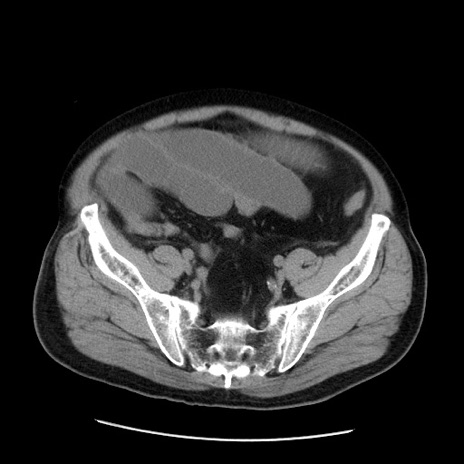

症例20(横断像)

【症例】 60歳代男性

【主訴】 腹部膨満、嘔吐

【現病歴】5日前頃より倦怠感を認め食事量減少し4日前の朝嘔吐、食事摂取困難となった。 3日前近医受診し点滴施行され整腸剤などを処方された。 当日他院を受診し、腹部膨満著明、炎症反応の上昇(CRP10.8、WBC11200)あり、紹介受診となる。

【身体所見】 意識JCS1 受け答えがはっきりしないBP 111/57mHg、 P 67bpm、、BT35.2°C、SpO2 97%(RA)、 腹部:膨隆、打診で鼓音あり、全体的に圧痛有り、腸蠕動音(-)、反跳痛ははっきりせず。

【データ】WBC 11400、CRP 14.20